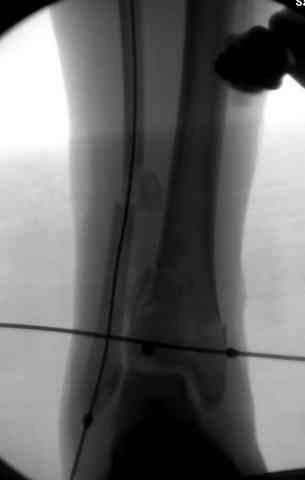

Яков изложил все необходимые аспекты лечения переломов пилона, и, не желая менять тему, решил выставить нашу точку зрения в двух клинических примерах.

При лечении внутрисуставных переломов типа "Pilon"

или "Tibial Plateau" на голени, применение простых

наружных фиксаторов типа "Spanning ExFix" или "Travelling ExFix" стал одним из стандартом этапного лечения.

В первые часы после поступления больным экстренно накладывается простой фиксатор из двух поперечно проведенных стержней или сооружается "Delta

Frame" в зависимости от места локализации, и проводится дистракция.

Здесь выставлена пара случаев перелома пилона, оба

случая леченные этапным наружным фиксатором.